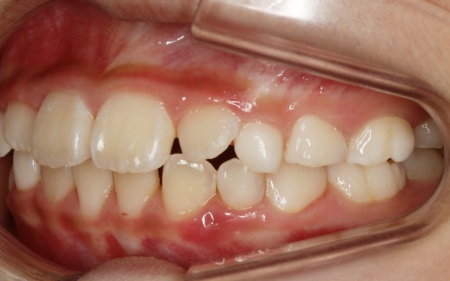

治療前

はじめの相談内容 「乳歯がデコボコに生えている。また、乳歯がギチギチに生えていて永久歯の生えるスペースがなさそうなので、早めに治療を始めたい」とご相談いただきました。

診断結果 拝見したところ、乳歯が隙間なく密集して生えている状態でした。

通常、乳歯の時期には歯と歯の間に発育空隙(はついくくうげき)と呼ばれる自然な隙間や、犬歯の前後に霊長空隙(れいちょうくうげき)と呼ばれる特徴的な隙間があります。

この隙間は、将来永久歯が生えるために必要なスペースを確保するためのものです。

しかし、患者様はこれらの重要な隙間がほとんど見られませんでした。

今のままでは、今後永久歯が適切な位置に並ぶためのスペースが不足すると考えられます。

以上のことから、永久歯への生え変わりをスムーズに進めるためにも、早急に治療を開始する必要があると診断しました。